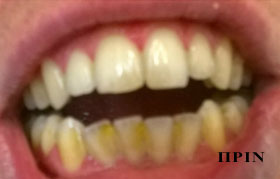

PHOTO GALLERY